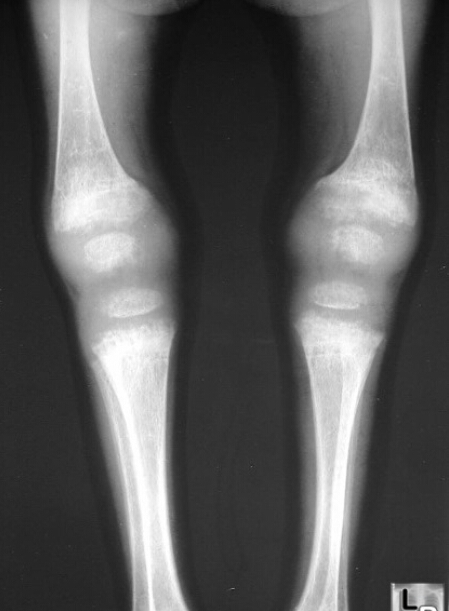

What is the diagnosis? What makes you think so?

Rickets

osteopenia, paintbrush metaphysis, lack of provisional zone of calcification

return of the zone is a sign of healing

fraying, splaying, bowing deformities, rachitic rosary